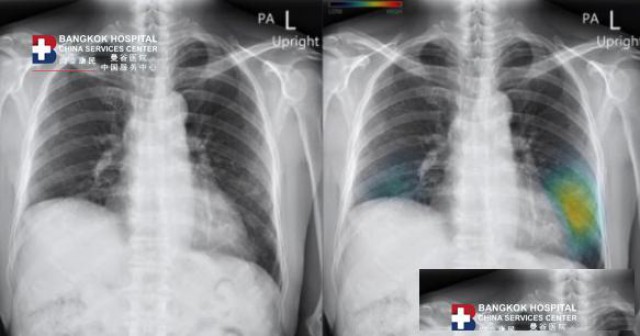

曼谷医院人工智能创新提高胸部X光的准确性

目前,放射科医师和放射科医务人员短缺被视为公共卫生领域的重要问题,这可能导致许多患者的诊断和治疗不得不延后,曼谷医院认识到重要性并选择一种创新的人工智能(Artificial Intelligence),Inspectra CXR是一款智能助理医师,能够详细、快速、准确、独特地分析胸片异常,能够直接解决医生的操作问题。

曼谷医院创新的人工智能或AI系统无需输入任何命令即可自动解读图像结果,报告结果通过放射科医生的操作屏幕即时显示,能适应每家医院不同的IT系统,并且还支持远程工作系统以及移动 X 射线检测装置。

曼谷医院Inspectra CXR系统是为提高医生工作效率而开发的人工智能软件,可以高度敏感地检测胸部 X 光图像上的病变,可以指示异常位置,尚泰康民——曼谷医院服务中心认为,人工智能技术是改变世界的技术,将不断进步,并可用于医学的各个领域,将更有效的有助于患者护理。